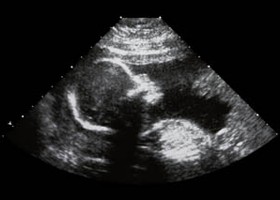

A nyitott gerinc magzati diagnosztikájában legfontosabb az ultrahang-vizsgálat. UH vizsgálat során feltűnő a homlok kidudorodása ("citrom-jel"), az agykamrák kitágulása, a kisagy összenyomódása és torzulása ("banán-jel"), továbbá az alsó végtagok fejletlensége és mozdulatlansága. A defektus helyén vagy nyílást, vagy a bőrfelület zsákszerű kiboltosulását láthatjuk.